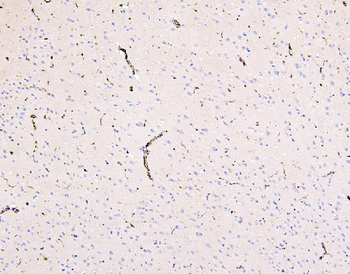

100 μg - PGP9.5 antibody [orb6713]Featured

ELISA, ICC, IF, IHC-P, WB

Human, Mouse, Rat

Rabbit

Polyclonal

Unconjugated